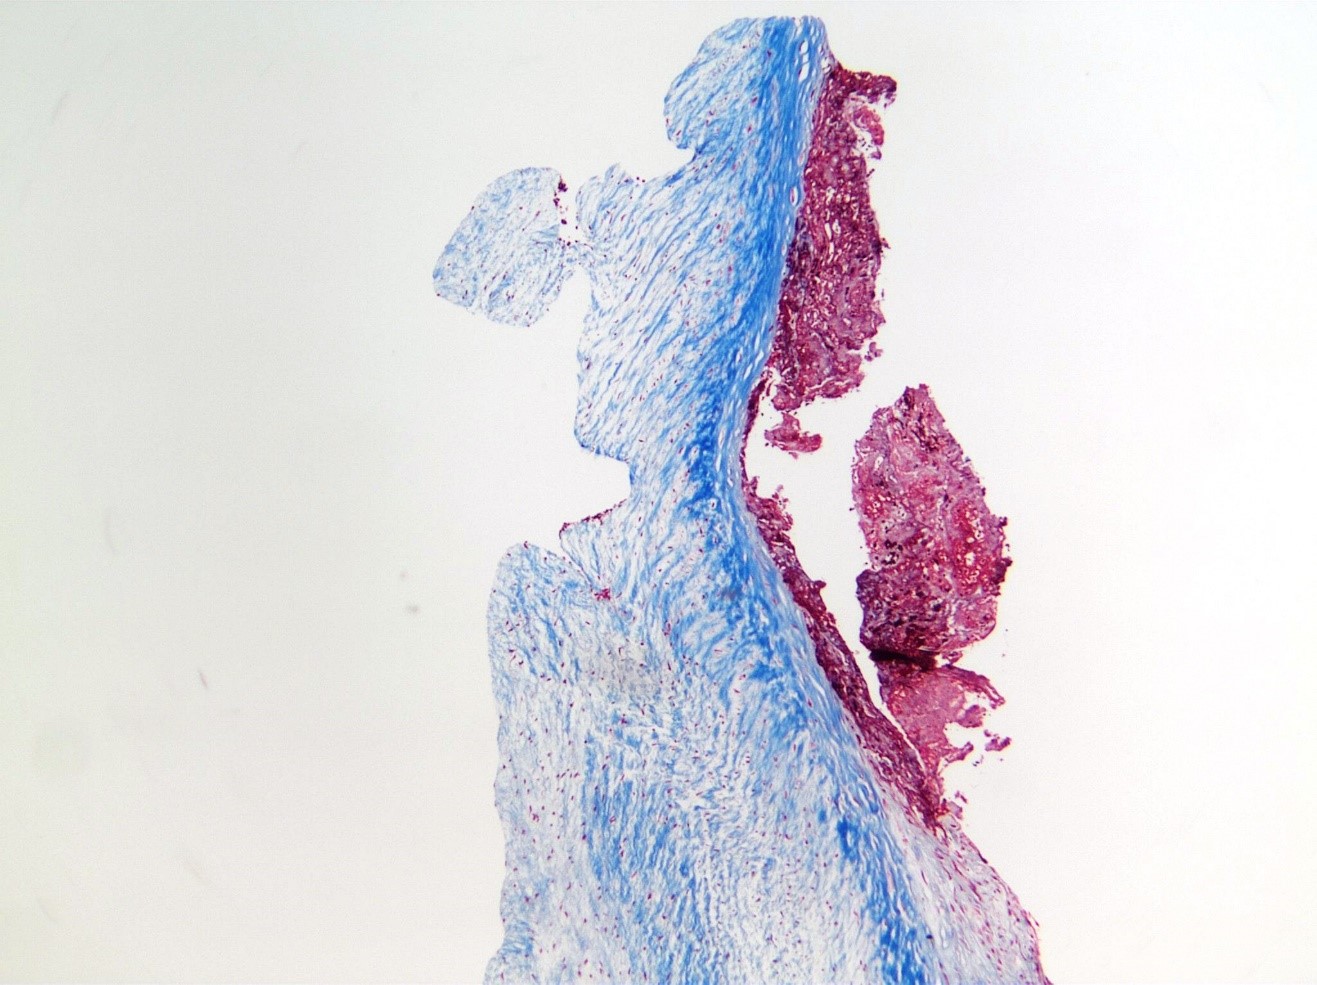

- Emergent debridement and resection of a 0.75 cm mass [Fig 6] from the anterior leaflet and repair of mitral valve with pericardial patch was performed.

- The mass was sent for pathology evaluation [Fig 7] and cultures. Infectious and rheumatologic work-up was negative.

- Pathology findings, recurrence and subsequent resolution with anticoagulation proved that this was a thrombus.

- Culture-negative infectious endocarditis must be ruled out with special stains, PCR, other techniques.